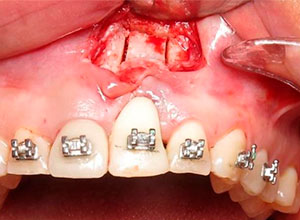

Decidimos hacer una corticotomia alveolar, dejando tejidos blandos en su lugar y cambiar la corona de cerámica por una corona de acrílico para cementar bien los brackets y poder empezar con la distracción.

Después de la corticotomia dejamos un tiempo de siete días para que se organizaran las células tisulares.

Se empezó a hacer la distracción, primero con un arco recto y posteriormente con elásticos haciendo el recorte con el borde incisal conforme se va bajando el implante con el bloque óseo.